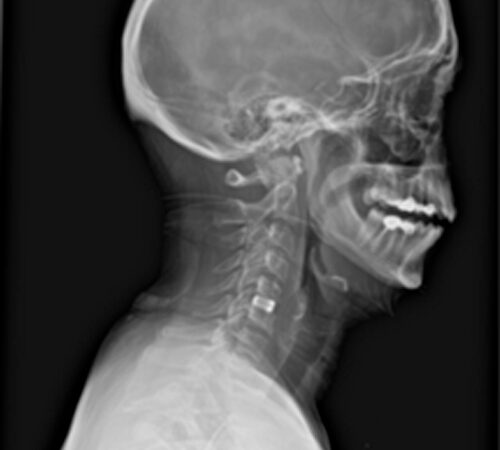

DIAGNOSI:

Ernia discale cervicale c5-c6

Risonanza magnetica cervicale pre-operatoria

Intervento chirurgico eseguito:

Microdiscectomia cervicale con approccio anteriore + introduzione di cage intersomatica cervicale

Radiografia cervicale post-operatoria